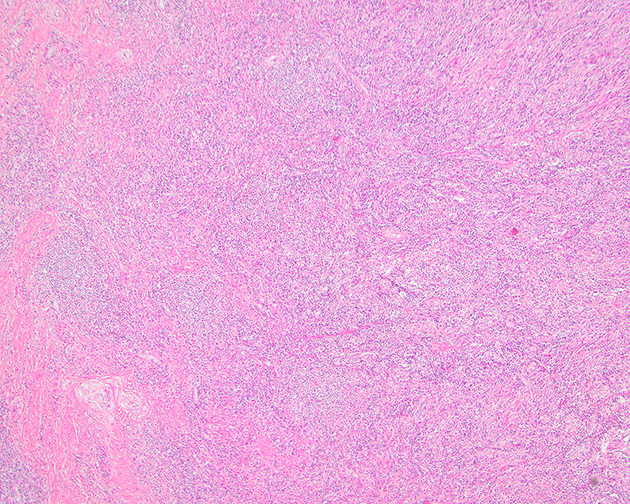

Microscopic (histologic) images

Contributed by Michael Clay, M.D., Melanie Bourgeau, M.D. and AFIP

Morphologic variability:

Microscopic (histologic) description

- Depends on subtype, generally composed of mature fat with variably sized adipocytes and bands of fibrotic stroma containing spindle cells with enlarged, hyperchromatic nuclei

- Can be markedly atypical

- Cellularity is low and mitotic figures are uncommon

- Atypical cells are more commonly found in fibrous septa and in a perivascular distribution

- Lipoma-like subtype

- Most common subtype

- Scattered atypical cells may be diffuse or exceedingly rare

- Frequently contains lipoblasts

- Grossly, can be indistinguishable from lipoma

- Sclerosing subtype

- Second most common subtype

- Predilection for retroperitoneal or paratesticular location

- Collagenous fibrous tissue with scattered adipocytes and atypical multinucleated stromal cells

- Scant lipogenic component may be missed in small samples

- Inflammatory subtype

- Rare

- Almost always in the retroperitoneum where it is confused with nonlipogenic tumors

- Chronic inflammatory cells (B > T cells) with occasional lymphoid follicles scattered in a cellular fibrocollagenous stroma with sparse multinucleated atypical cells

- May obscure adipocytes